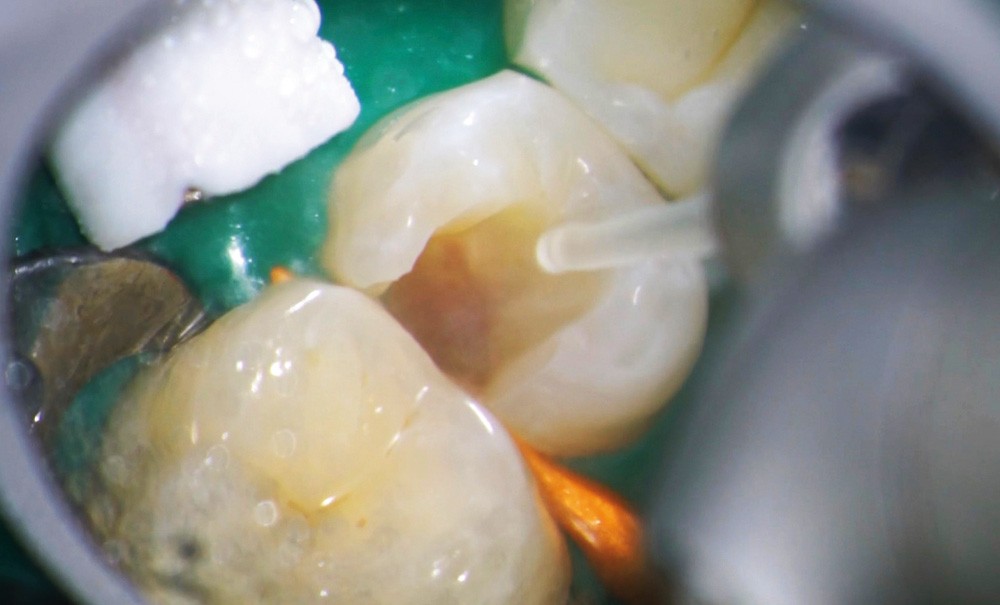

Le laser Erbium s’insère donc parfaitement dans nos principes actuels de traitements mini-invasifs comme activateur de nos solutions d’irrigation (fig. 1a à c).

Le laser Er:YAG va permettre une élimination des débris en surface, une stérilisation, avec comme irrigation de l’eau stérile [36] et en coupant le spray, une hémostase avec la formation d’une couche de coagulation [37] propre à la formation d’un pont dentinaire au contact du biomatériau, qui peut être bio-actif, tel que la Biodentine (Septodont) (fig. 6a à d).

Protocole opératoire : sous anesthésie, une cavité suffisante à recevoir le biomatériau (2 à 3 mm) sous champ opératoire est réalisée. La désinfection au laser Er:YAG (40 mJ ; 20 Hz) sous spray, pendant 20 secondes, est alors mise en œuvre. S’en suit éventuellement une coagulation de 3 secondes, en coupant le spray, puis la mise en place du biomatériau Biodentine (Septodont). Il sera ensuite recouvert d’un matériau de restauration adéquate.